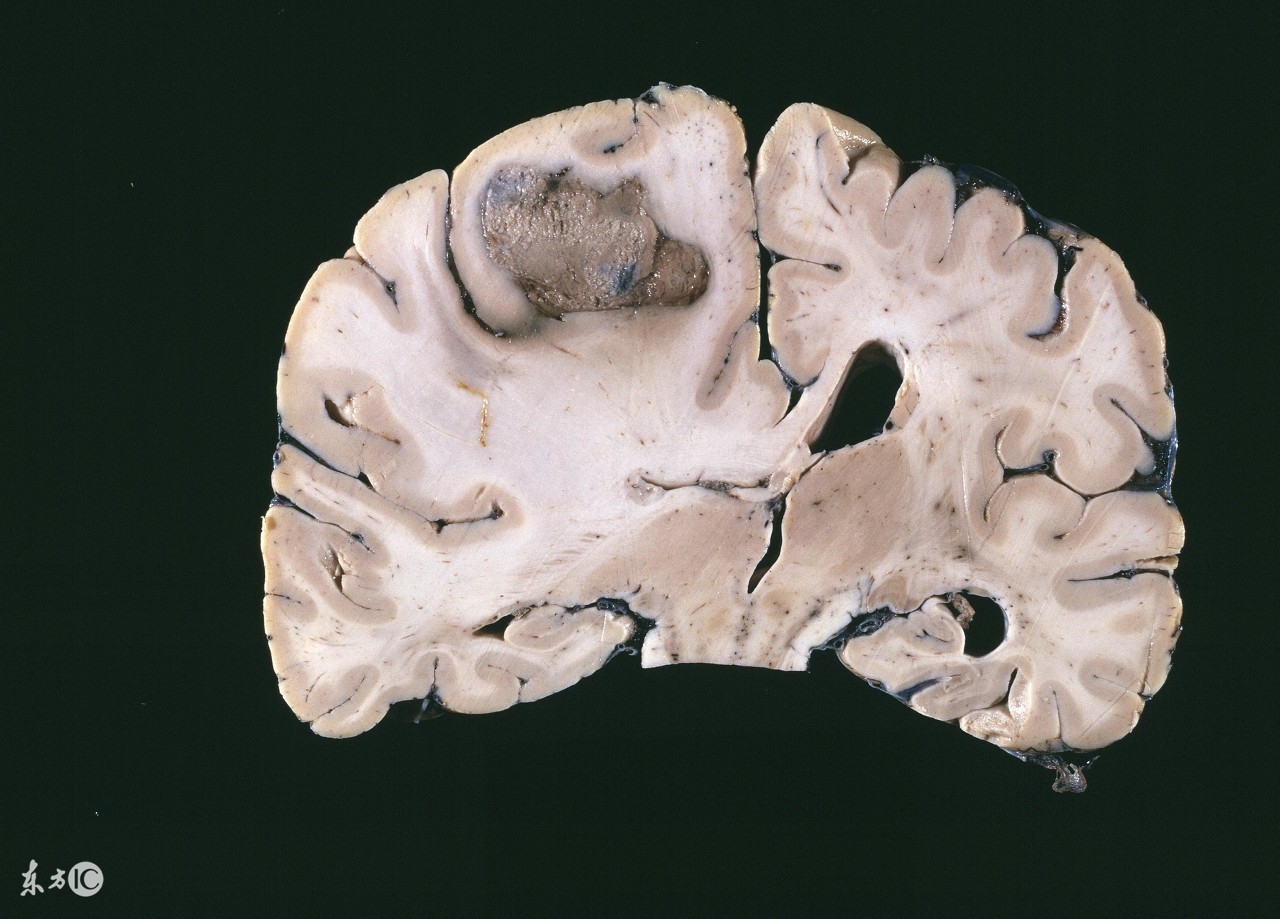

脑瘤是一种会严重影响患者脑神经系统的疾病,生活中,患有脑瘤的患者并不在少数,由于这种疾病对于患者的危害非常大,所以及时有效的治疗是很重要的,随着我国医学技术的不断进步,治疗脑瘤的方法是有很多种的,但是如果这种疾病发展到晚期应该怎么办呢?下面我们就来根据这个问题来进行一下详细的介绍。